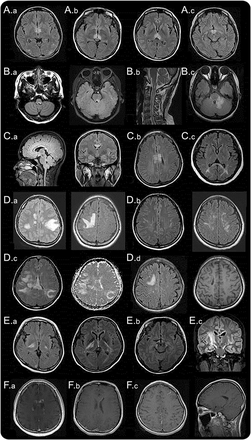

间脑的第三脑室和脑导水管周围病变。

间脑的第三脑室和脑导水管周围的病变,包括丘脑、下丘脑、中脑的前边缘在NMOSD已报告(图1一个)。10,12这些病变通常无症状,但有些病人可能有抗利尿激素分泌不当综合征,e6嗜睡症,e7体温降低,低血压,嗜睡,肥胖,e8甲状腺功能减退、高泌乳素血症、继发性闭经、乳溢和行为变化。e9

间脑的病变周围(一)第三脑室和脑导水管,(A.b),包括丘脑、下丘脑、中脑的前边缘(交流)。(本科)背脑干损伤邻近第四脑室,(反方向)线性髓病变与颈脊髓损伤,相邻(公元前)水肿和大量的背侧脑干病变涉及小脑脚。(一个)立即胼胝体病变侧脑室,室管膜衬后,(C.b)“大理石模式”胼胝体的病变,(运费到付)“拱桥模式”胼胝体的病变。块状半球白质病变,簇状(地方检察官)(D.b)长spindle-like或放射状病变白质束后,(特区)广泛和汇合的半球病变显示表观扩散系数地图上增加扩散系数表明vasogenic水肿,(d)在慢性阶段半球病变显示cystic-like腔的变化。(E.a)皮质脊髓束损伤涉及的内囊后肢和中脑(后代e.b.)大脑脚(欧共体)纵向锥体束后广泛的病变。(范围内)的云雾状增强(F.b)侧脑室的室管膜表面的线性增强,(F.c)脑膜增强。

背侧脑干病变毗邻第四脑室。

最具体的脑部MRI异常患者NMOSD是背脑干病变毗邻第四脑室包括postrema面积和细胞核大港solitarius。这种病变是高度与顽固性呃逆,恶心、呕吐,10,12,21和在7%到46%的已报告NMOSD患者。12,15e1, e10汽油这个区域,催吐的反射中枢,没有那么严格的血脑屏障,使它更容易AQP4-IgG攻击。核磁共振以及临床证据支持这一概念,区域postrema NMOSD患者是一个重要的点的攻击,进一步表明,这一地区是一个门户循环免疫球蛋白进入中枢神经系统。22,23病理异常被发现在这一地区40%的患者动,但没有明显的神经元,轴突或髓鞘的损失。21髓损伤与颈脊髓损伤通常是连续的,通常采取线性形状(图1反方向)。这些病变可能与疾病的最初症状22,24或预示急性恶化。25各种脑干病变可能出现相应症状,如眼球震颤、构音障碍、吞咽困难、共济失调、眼肌麻痹。15,20.、e11 e12汽油

Periependymal侧脑室周围的病变。

在胼胝体病变中描述NMOSD患者的12%到40%。12,15,26因为动校正和女士经常有胼胝体的病变,本身并不是一个独特的位置发现NMOSD有别于然而女士,女士的胼胝体的病变是离散的,卵形的,垂直于心室和涉及胼胝体的低等方面(图2一个),e13, e14灯头NMOSD病变位于侧脑室立即旁边,后室管膜衬(图1一个)。12急性胼胝体的病变NMOSD经常水肿和异构,创建一个“大理石的模式”26有时涉及完整的厚度压部在一个独特的“拱桥模式”(图1中,C。b和运费到付)。12有时,大脑半球的胼胝体病变延伸到,形成一个广泛和汇合的白质病变。12NMOSD在慢性阶段,胼胝体的病变往往规模和强度降低,甚至消失26;然而,囊性变化,描述了胼胝体萎缩。e15某些临床症状,如认知和运动协调障碍,可能归因于胼胝体的病变,但他们还没有被很好地评估。

半球的白质病变。

广泛和汇合的半球的白质病变是块状(> 3厘米直径最长)簇状经常或长期以来spindle-like放射状白质束(图1 d)。12质量效应通常是缺席的。e16天病灶扩散系数增加表观扩散系数地图上表明vasogenic水肿与急性炎症(图1特区),12,27偶尔模仿后部可逆性脑病综合症28或Balo病变。e17, e18发现了这些广泛病变更频繁地在anti-AQP4抗体血清反应阳性的血清反应阴性的病人。29日在慢性阶段,这些大病变倾向于缩小甚至消失,但是在某些情况下,cystic-like或空洞的变化显示(图1所示的代码)。e19, e20这些病变可能导致各种症状如轻偏瘫、脑病、视野缺陷取决于它们涉及的面积。大汇合的半球的白质病变与NMOSD孩子并不罕见。Tumefactive病灶周围水肿带和变量质量效应可能类似于急性播散性脑脊髓炎20.,30.或中枢神经系统恶性肿瘤。31日

病变包括皮质脊髓束。

病变包括皮质脊髓束可以单边或双边、并可能延长从深在大脑半球白质内囊后肢的到达大脑总花梗中脑、脑桥(图1 e)。12这些病变是连续的,通常纵向广泛,锥体束后(图1欧共体)。皮质脊髓束损伤被发现在23%到44%在一些群NMOSD患者12、e2在其他军团,偶尔被报道。11,13这是感兴趣的,与circumventricular地区,皮质脊髓束不AQP4的地区是高度表达;尚不清楚为什么这些地区也经常参与NMOSD。